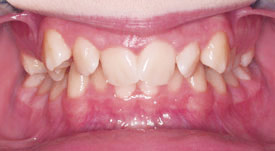

Crossbite